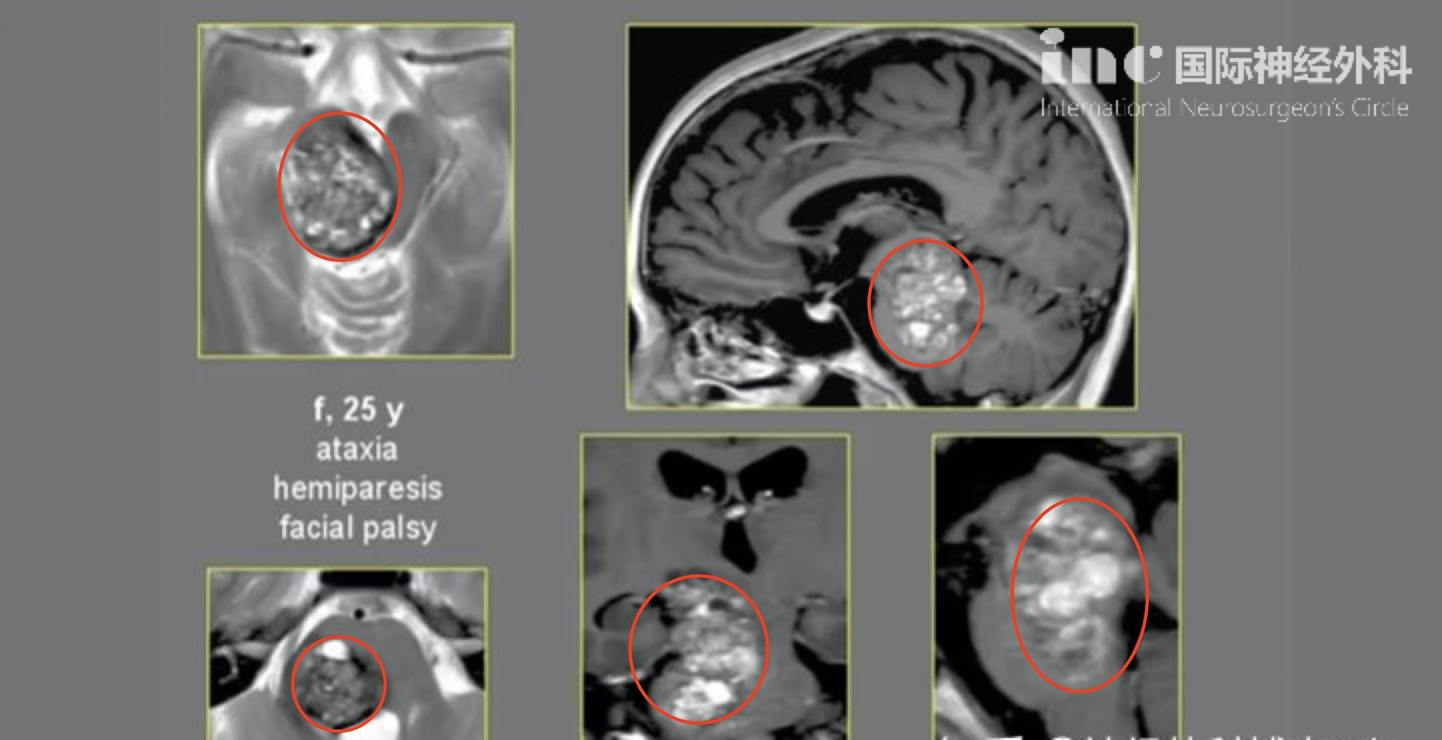

病患基本情況:25歲女性,肢體癱瘓、面癱,共濟失調(diào)

診斷:(中腦-腦橋)腦干較大海綿狀血管瘤。術前影像:中腦、腦橋較大占位

腦干海綿狀血管瘤手術案例

手術結果:腦干內(nèi)海綿狀血管瘤全切,歷時2小時,手術順利

術后恢復:無新發(fā)神經(jīng)功能損傷,術前癥狀明顯好轉,肢體癱瘓、面癱好轉,能自行獨自行走,治療效果滿意。

(術后MR顯示腫瘤全切,病人面癱、肢體偏癱明顯好轉,能自行行走)